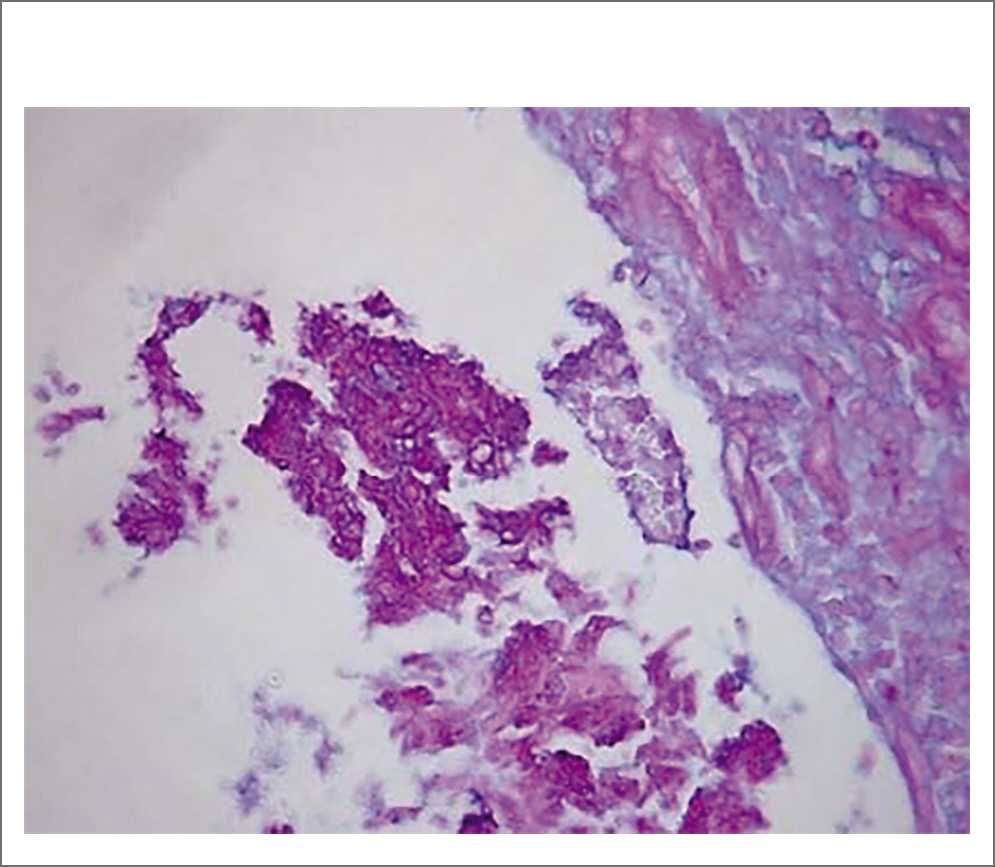

Через 10 дней получен ответ с описанием признаков хронического воспаления и полипоза носа: отечная, фиброзная или слабомиксоидная строма, инфильтрирована смешанными воспалительными клетками, включая лимфоциты, плазматические клетки, эозинофилы, нейтрофилы и тучные клетки, поверхностный эпителий проявляется изъязвлением или плоскоклеточной метаплазией, подслизистые железы уменьшены или отсутствуют. Заключение гистологического исследования: множественные аденоматозные фиброзно-отечные полипы носа. Данные за мицелий отсутствуют (рис. 5–7). После обращения с просьбой повторно исследовать гистологические блоки на наличие грибов морфологами были использованы элективные методы обработки (постановка ШИК-реакции, метод Гомори) и обнаружены элементы мицелия грибов (рис. 8). Импрегнация по Гомори–Грокотт метинамином серебра не проводилась.

Рис. 8. Элементы мицелия грибов. ШИК-реакции.